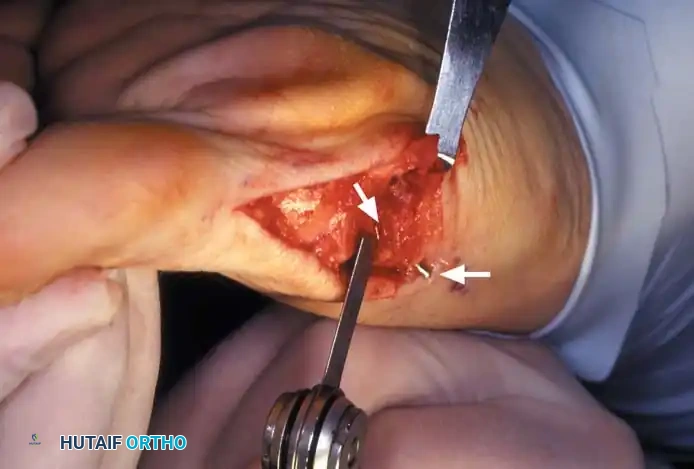

• Using a Freer elevator or a small osteotome for its strength, mobilize the fi bular sesamoid (Fig. 78-31A to C). This may be diffi cult in elderly patients with signifi cant deformity and adherence of the sesamoid to the metatarsal head. Lift the metatarsal dorsally for exposure (Fig. 78-31D and E).

• Incise the intersesamoid ligament longitudinally with a No. 67 Beaver or No. 15 Bard-Parker blade. If tenotomy scissors are used, place one arm of the scissors under the ligament (this arm rests on the dorsal side of the fl exor hallucis longus) and the other arm dorsal to the ligament.

• When the intersesamoid ligament is incised, grasp the sesamoid fi rmly with forceps or a small Kocher clamp, fl ex the toe at the interphalangeal and metatarsophalangeal joints to relax the fl exor hallucis longus tendon, and pull the fi bular sesamoid distally and medially.

• With release of the intersesamoid ligament, the medial surface of the fi bular sesamoid is free from soft tissue. Distally, the sesamoid is free because of resection of the base of the proximal phalanx. This leaves two sides of the sesamoid, distal and medial, free of soft tissue.

• While pulling the sesamoid distally and medially, use a small blade to incise along the lateral margin of the sesamoid under direct vision. Keep pulling the head of the metatarsal dorsally and holding the hallux distracted and in fl exion. This greatly aids in identifi cation of the margins of the fi bular sesamoid, particularly laterally and proximally.

• The most diffi cult part of the sesamoidectomy and that which should be done last is release of the proximal lateral corner of the sesamoid where the fl exor hallucis brevis lateral head inserts. While incising the lateral capsular attachments to the sesamoid, do not bury the blade of the knife because the neurovascular bundle to the lateral side of the hallux is just lateral to the capsule.

• Now all attachments to the fi bular sesamoid have been removed except the lateral head of the fl exor hallucis brevis, which inserts on the proximal lateral margin of the sesamoid. This is a diffi cult section to remove; however, this section can be released under direct vision by pulling the sesamoid distally and medially and lifting the metatarsal head dorsally with a strong two-toothed retractor.

Fig. 78-31 Excision of fi bular sesamoid in modifi ed Keller procedure. With base of proximal phalanx removed and medial eminence excision, exposure of fi bular sesamoid is not as diffi cult from medial incision. A, Operative photograph showing elevation of fi rst metatarsal with strong two-tooth retractor and use of small osteotome to mobilize fi bular sesamoid and lateral capsuloligamentous (frequently contracted) structures. Osteotome is between metatarsal head and lateral sesamoid. When mobilization of fi bular sesamoid is complete, entire sesamoid is visible for excision. Note chondromalacia of tibial sesamoid articular surface medial to osteotome. B, Fibular sesamoid has been excised, and lateral capsular structures and conjoined tendon (in forceps) have been released. Neurovascular bundle to lateral side of hallux is adjacent to these structures. C, Diagrammatic representation of modifi ed Keller procedure. By excising fi bular sesamoid, valgus moment of conjoined tendon of fl exor hallucis brevis and adductor hallucis no longer pulls fl exor hallucis longus tendon laterally (carrying hallux with it) through capsulosesamoid plantar plate and pulley system. D, Metatarsal head must be lifted dorsally to excise fi bular sesamoid under direct vision. E, Note exposure of fi bular sesamoid after mobilization of metatarsal head. Continued